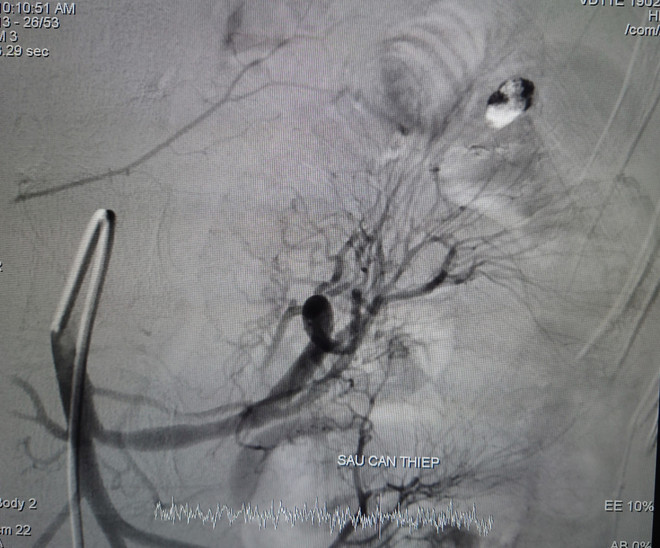

Ổ thoát mạch sau can thiệp. (Ảnh: TTXVN phát)

Các bác sỹ tiến hành chọn lọc vào nhánh thoát mạch, xác định vị trí, tiến hành bơm hỗn hợp keo và kiểm tra thấy tắc hoàn toàn nhánh thoát mạch. Thời gian can thiệp là 45 phút.

Các bác sỹ tiến hành hội chẩn, quyết định chụp và nút động mạch điều trị cầm máu trên máy chụp mạch số hóa xóa nền (DSA). Êkíp can thiệp ghi nhận ổ thoát mạch từ ruột non được cung cấp máu từ nhánh động mạch mạc treo tràng trên.